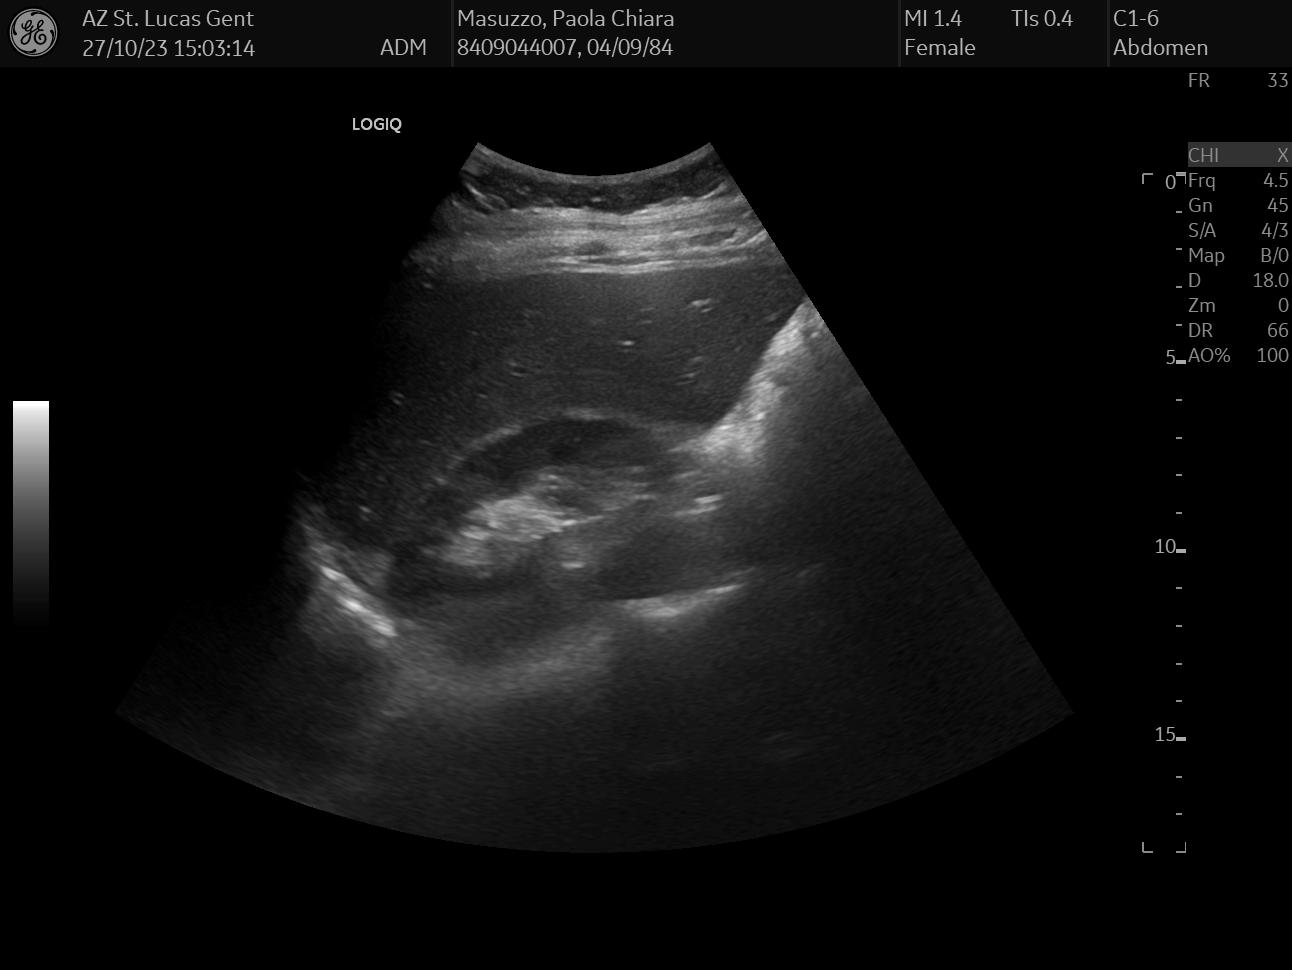

On the same day, I also had an abdomen ultrasound of my liver, gallbladder, and bile duct, which together can paint a pretty accurate status of your hepatic health - or lack thereof.

Like with any ultrasound exam carried over by a physician, the visit was pretty painless and I got the results on the spot: everything looked pretty normal. For this exam, I selected random data: I chose 3 images that looked the funniest to me, but I honestly have no idea what they mean.